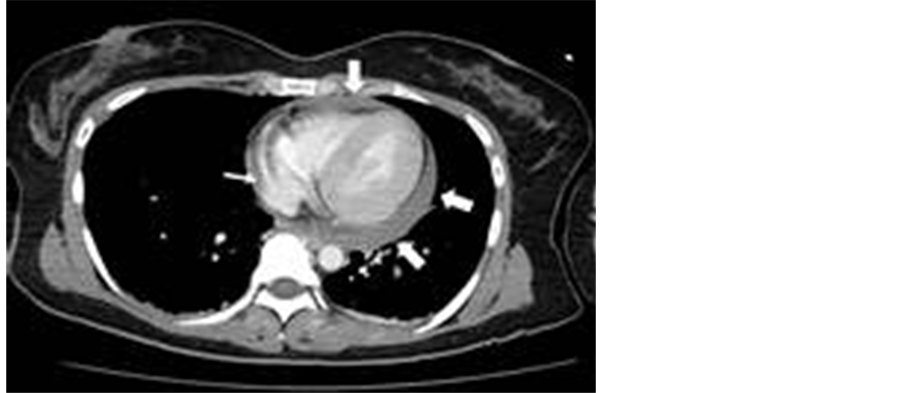

A 36-year-old female was transferred to our tertiary hospital 50 minutes after a high-speed car crash. On arrival, she was pale and distressed and had a heart rate of 163 bpm and a blood pressure of 63/55 mmHg. Pericardial effusion was detected with FAST after she presented with cardiac tamponade. The patient was immediately referred to a cardiovascular surgeon. Tracheal intubation was performed, and an arterial line was quickly installed to enable careful monitoring. The patient’s heart rate and systolic blood pressure remained above 150 bpm and 60 mmHg, respectively, after fluid resuscitation and dopamine administration. After taking the patient’s unchanged vital signs and the time elapsed since the accident into consideration, we decided to perform pericardial drainage via pericardial decompression in the ER due to a concern about uncontrollable hemorrhaging, as the patient collapsed whenever she attempted to stand. A contrast-enhanced computed tomography scan revealed pericardial effusion and the extravasation of contrast medium from at least two portions of the right atrium (Figure 1). In addition, liver and right kidney injuries were identified. The patient was moved to the OR as soon

Figure 1. Contrast-enhanced computed tomography shows contrast extravasation from right atrium (thin arrow) and pericardial effusions (thick arrow).

as possible (approximately one hour after the patient’s arrival). A median sternotomy was performed followed by pericardiotomy, which raised the patient’s systolic blood pressure to over 150 mmHg. Two tears of 5 mm in length were found in the right atrial appendage, which were successfully repaired without CPB. The patient required four units of RBC within 24 hours of her arrival. Her postoperative course was uneventful, and she was discharged on day 22.